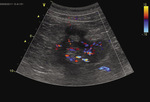

U 75-letniego mężczyzny wykonano w trybie ambulatoryjnym kolejne badanie USG jamy brzusznej. Pacjenta monitorowano ze względu na wcześniejsze uwidocznienie torbieli w obu nerkach. Obraz zmian sugerował występowanie nabytej torbielowatości nerek.1,2 Obserwowano kilka zmian bezechowych, których średnica powolnie przyrastała w kolejnych, wykonywanych co kilka lat badaniach USG. Chory nie zgłaszał żadnych dolegliwości, wydolność nerek oceniana w badaniach laboratoryjnych także była zachowana. Wyniki badań biochemicznych krwi oraz moczu były prawidłowe (u pacjenta wykonywano badania kontrolne ze względu na łagodny przerost gruczołu krokowego). Badanie USG jamy brzusznej wykazało obecność kilku zmian o cechach torbieli różnej wielkości, zlokalizowanych w obrębie obu nerek. Największa zmiana w dolnym biegunie nerki lewej miała typowy obraz – dobrze odgraniczona przestrzeń bezechowa. Zmiana o cechach torbieli opisywana w poprzednich badaniach, zlokalizowana na zewnętrznym obrysie nerki lewej, obecnie miała niejednorodną echostrukturę. W badaniu zastosowano opcję dopplerowską (CD – color doppler), nie wykazano jednak cech patologicznego unaczynienia w obrębie zmiany (ryc. 1).